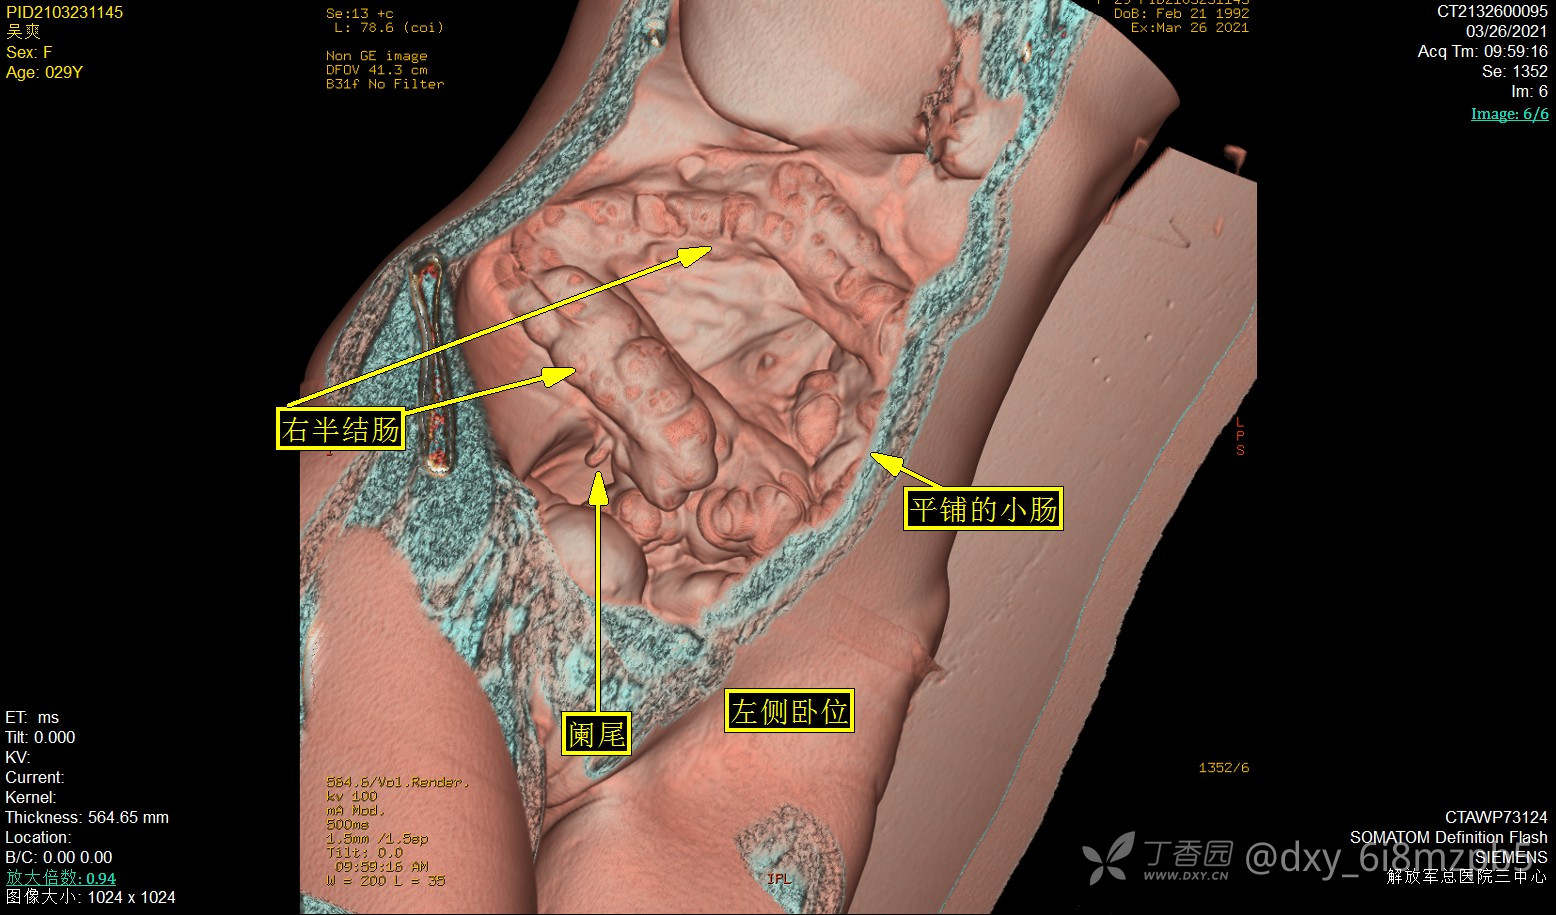

左侧卧位图:显示更多右半结肠形态细节,见回盲部阑尾,末端回肠近乎正常形态。

右侧卧位图:显示小肠粘连团呈圆锥体,与乙状结肠粘连。

患者腹膜腔形态排除前腹壁粘连。侧卧位腹腔内位器官(小肠襻)发生重力位移,可确认有回肠襻团与乙状结肠有挂壁粘连。该粘连范围局限,无肠管扭曲,无口径异常,易于松解,无法认作肠梗阻的责任粘连。依据回肠襻在侧卧位、俯卧位的形态,极有可能存在肠襻间脏性粘连。其形态符合或支持其为梗阻病因,尚不显著。

回肠肠管间脏性粘连有两处病史辅证:2012年潍坊市肿瘤医院全消化道钡餐报告。2014潍坊市第一人民医院腹腔镜探查。家属转述腹腔镜手术仅作探查,因广泛粘连而放弃。该粘连是否存在,是否和腹膜腔虚拟图像吻合,能否合理解释肠梗阻反复发作的机制,是术前的困惑之处。腹腔内梗阻病变仍有相当大的不确定性,有待腹腔镜探查确认。